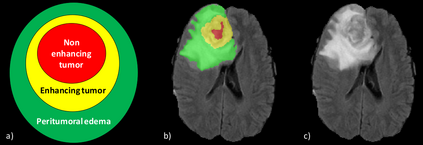

Training a deep neural network is an optimization problem with four main ingredients: the design of the deep neural network, the per-sample loss function, the population loss function, and the optimizer. However, methods developed to compete in recent BraTS challenges tend to focus only on the design of deep neural network architectures, while paying less attention to the three other aspects. In this paper, we experimented with adopting the opposite approach. We stuck to a generic and state-of-the-art 3D U-Net architecture and experimented with a non-standard per-sample loss function, the generalized Wasserstein Dice loss, a non-standard population loss function, corresponding to distributionally robust optimization, and a non-standard optimizer, Ranger. Those variations were selected specifically for the problem of multi-class brain tumor segmentation. The generalized Wasserstein Dice loss is a per-sample loss function that allows taking advantage of the hierarchical structure of the tumor regions labeled in BraTS. Distributionally robust optimization is a generalization of empirical risk minimization that accounts for the presence of underrepresented subdomains in the training dataset. Ranger is a generalization of the widely used Adam optimizer that is more stable with small batch size and noisy labels. We found that each of those variations of the optimization of deep neural networks for brain tumor segmentation leads to improvements in terms of Dice scores and Hausdorff distances. With an ensemble of three deep neural networks trained with various optimization procedures, we achieved promising results on the validation dataset of the BraTS 2020 challenge. Our ensemble ranked fourth out of the 693 registered teams for the segmentation task of the BraTS 2020 challenge.